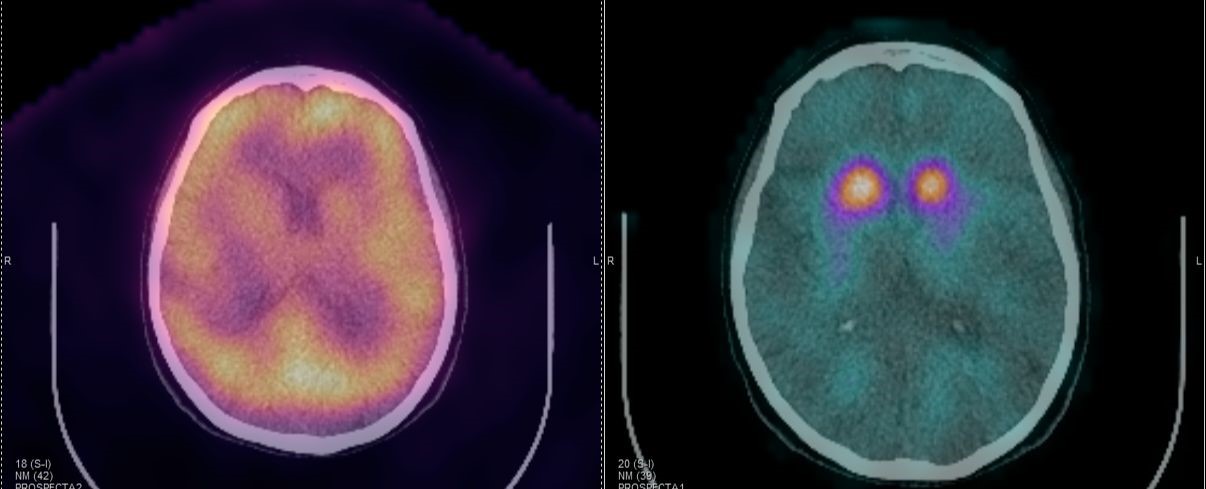

IQ SPECT Η τέχνη της ελαχιστοποίησης της δόσης με ταυτόχρονη μεγιστοποίηση της ταχύτητας Στη σύγχρονη Πυρηνική Ιατρική, όπου η ανάγκη για ταχύτερες και ασφαλέστερες μελέτες Μυοκαρδιακής Αιμάτωσης (MPI) αυξάνεται διαρκώς, το IQ SPECT αποτελεί μία από τις πλέον ώριμες και καινοτόμες τεχνολογίες. Η αρχή του είναι απλή και καθαρή: να συλλέγει όσο το δυνατόν περισσότερα δεδομένα από την καρδιά, με την ελάχιστη δυνατή δόση και στον ελάχιστο χρόνο, χωρίς συμβιβασμούς στην ποιότητα εικόνας. Minimum dose & maximum speed Στις συμβατικές SPECT καρδιάς, μεγάλο τμήμα του ανιχνευτή δεν αξιοποιείται λόγω του μικρού μεγέθους του εξεταζόμενου οργάνου. Αυτό οδηγεί σε παρατεταμένο acquisition – πολλές φορές έως 16 λεπτά – ώστε να εξασφαλιστεί η αναγκαία ποιότητα εικόνας. Το IQ SPECT υπερβαίνει αυτόν τον περιορισμό. Με βελτιστοποιημένο χειρισμό της γεωμετρίας, των collimators και του acquisition, μεγιστοποιεί τα ανιχνευόμενα δεδομένα από την καρδιά, επιτρέποντας ολοκληρωμένη μελέτη σε λιγότερο από 5 λεπτά, μείωση της χορηγούμενης δόσης έως και 75%, και διατήρηση ή και βελτίωση της ποιότητας εικόνας.